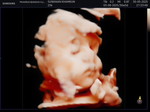

33w2d อาการเล่านี้ปกติใช่มั้ยคะแม่ๆ

1.เวลานั่งลูกถีบสูงมากค่ะ บริเวณใต้ราวนม นั่งปกติแทบไม่ได้เลยค่ะ เหมือนไปเบียดตัวลูก เวลานอนตะแคงซ้ายก็ถีบแรงมาก 2. 2-3วันมานี้ เวียนหัวเหมือนจะหน้ามืดบ่อยมากค่ะ เป็นเวลาลุกเดินตลอด หายใจไม่ทั่วท้องเลยค่ะ เหนื่อยมาก 3.นั่งรถมอไซต์ หรือนั่งกินข้าวนานๆรู้สึกปวดที่มดลูกมากค่ะ บางครั้งก็เจ็บแปล๊บๆเหมือนโดนช็อต และปวดตรงขาหนีบ บางทีแทบไม่มีแรงเดินเลยค่ะ 4.ตกขาวเยอะขึ้นกว่าแต่ก่อน แยกไม่ออกด้วยค่ะอันไหนตกขาวอันไหนมูก กังวลมากค่ะ 5.บางทีรู้สึกปวดจี๊ดๆที่ท้อง บางครั้งก็ปวดฝั่งซ้าย บางครั้งก็ปวดฝั่งขวา 6.มีอาการท้องแข็ง แต่ไม่บ่อย อาการเล่านี้ลูกกลับหัวหรือยังคะ พอดีไปตรวจตามนัดหมอไม่ได้แจ้งอะไรเลยค่ะ